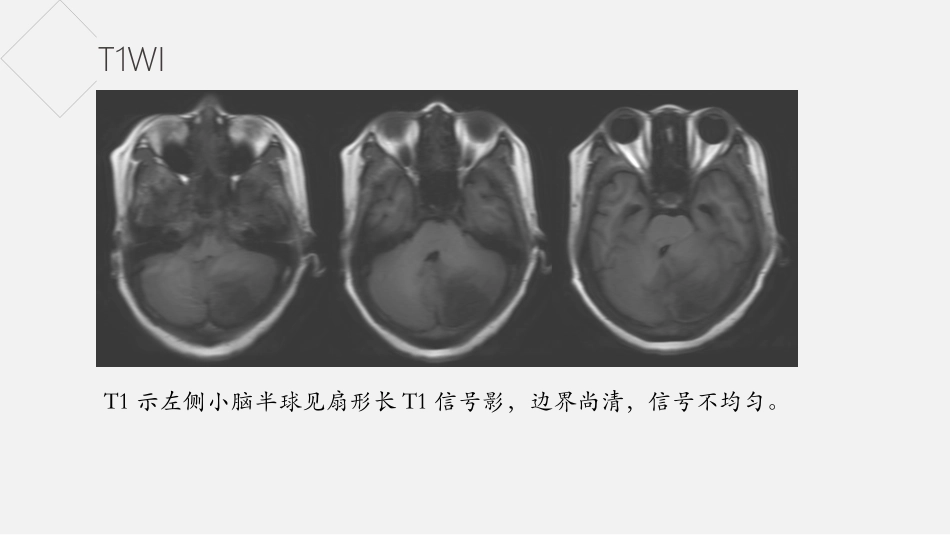

病史女,42岁,3天前无明显诱因出现头晕不适,精神食欲差,当地医院提示左侧小脑半球占位性病变。T2WIT2示左侧小脑半球见扇形长T2信号影,边界尚清,信号不均匀。T1WIT1示左侧小脑半球见扇形长T1信号影,边界尚清,信号不均匀。DWIADCDWI示左侧小脑半球病灶呈稍高信号,ADC示病灶部分呈低信号。增强增强示病灶未见明显强化。小脑发育不良神经节细胞瘤小脑发育不良神经节细胞瘤概述Padberg等人认为小脑发育不良神经节细胞瘤与多发性错构瘤综合征(MHAM)(也称为Cowden综合征(CS))共存的观点,认为PTEN基因突变是导致CS的主要原因。CS是一种常染色体显性遗传性癌症综合征,其特征在于通过与乳腺癌,甲状腺癌和泌尿生殖恶性肿瘤、全身错构瘤等高发生率相关联的神经皮肤综合征。2007年WHO分类中将本病归属神经元和混合性神经元的神经胶质肿瘤,并统一命名为小脑发育不良性神经节细胞瘤属良性肿瘤(WHOⅠ级)。小脑发育不良神经节细胞瘤临床症状本病进展较缓,早期症状轻微;部分患者无症状在体检时发现。其首发症状多以颅内高压症为主要表现,如头痛、恶心、呕吐、视物模糊等;其次为后组颅神经麻痹,小脑症状如共济失调、步态不稳等一般出现较晚。临床上常伴有多种先天发育畸形,如巨脑、脊髓积水、多指(趾)、多发血管瘤和颅骨异常。无明显性别及种族差异,年龄跨度较大,从出生至74岁均可发生,发病年龄高峰为30~50岁。小脑发育不良神经节细胞瘤病理组织学形态可见弥漫性增厚的小脑分子层和颗粒层内大量异常增生的神经节细胞,使小脑皮质增宽,但原有结构仍相对保留;分子层外可见平行排列的异常有髓纤维;浦肯野细胞减少或消失,亦可见扩张血管和钙化灶。免疫组织化学染色,异常神经节细胞胞核表达神经元核抗原(NeuN,图2)和突触素(Syn)、而不表达同源性磷酸酶张力蛋白(⁃PTEN),胶质纤维背景表达胶质纤维酸性蛋白(GFAP),神经纤维表达神经微丝蛋白(NF)。小脑发育不良神经节细胞瘤影像表现T2WI呈现高信号区域内有低信号的条纹状排列结构,T1WI呈等/低信号条纹,这种条纹排列结构称之为“虎纹征”。病灶边界清晰,周围无水肿。增强扫描病变无明显强化或轻微强化。通常伴梗阻性脑积水、小脑扁桃体疝、脊髓空洞。谢谢欣赏